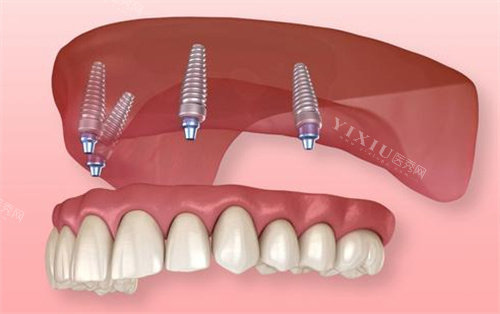

Locator半固定种植牙是一种结合了固定种植与活动义齿特点的修复方式。它通过植入少量种植体(通常半口2-4颗)作为支撑,再使用Locator基台连接可摘卸义齿,在确保一定稳定性的同时,兼顾了清洁便利性和经济性。

Locator半固定种植系统的工作原理是通过植入2-4颗种植体作为基础支撑,利用特殊的Locator基台将义齿与种植体连接。这种基台包含弹性连接器,形成半固定结构,使义齿既保持一定稳定性,又能够自行摘戴。

在稳定性方面,Locator半固定种植明显优于传统活动假牙,固位力更强,咀嚼效率有显著提升。但与全固定种植牙相比,其稳定性稍逊一筹。这种修复方式特别适合牙槽骨吸收较为严峻、颌间距较大,或者由于各种原因无法植入多颗种植体的患者群体。